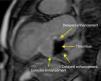

In view of the patient's dyspnea and recurrent chest pain, without new electrocardiographic alterations or elevation of myocardial necrosis markers, thoracic CT was performed, which showed a hypodense mass, apparently extracardiac, next to the left atrium. A second echocardiogram showed a mass (39mm×40mm) adjacent to the left atrium, but continuity with the cardiac chambers was not conclusively demonstrated (Figures 1 and 2). Subsequent cardiac magnetic resonance imaging revealed a large left ventricular inferobasal aneurysm, partly filled by a large thrombus (52mm×48mm×32mm). Given the thinness of the aneurysm wall, it was impossible to distinguish different layers, and so pseudoaneurysm with late presentation could not be definitively excluded. There was some flow between the thrombus and the aneurysmal sac, but the former appeared to be adhering to the upper and lower walls of the aneurysm (Figures 3 and 4). The exam also confirmed severe left ventricular dysfunction and mitral regurgitation due to changes in left ventricular geometry, with marked posterior leaflet tethering.